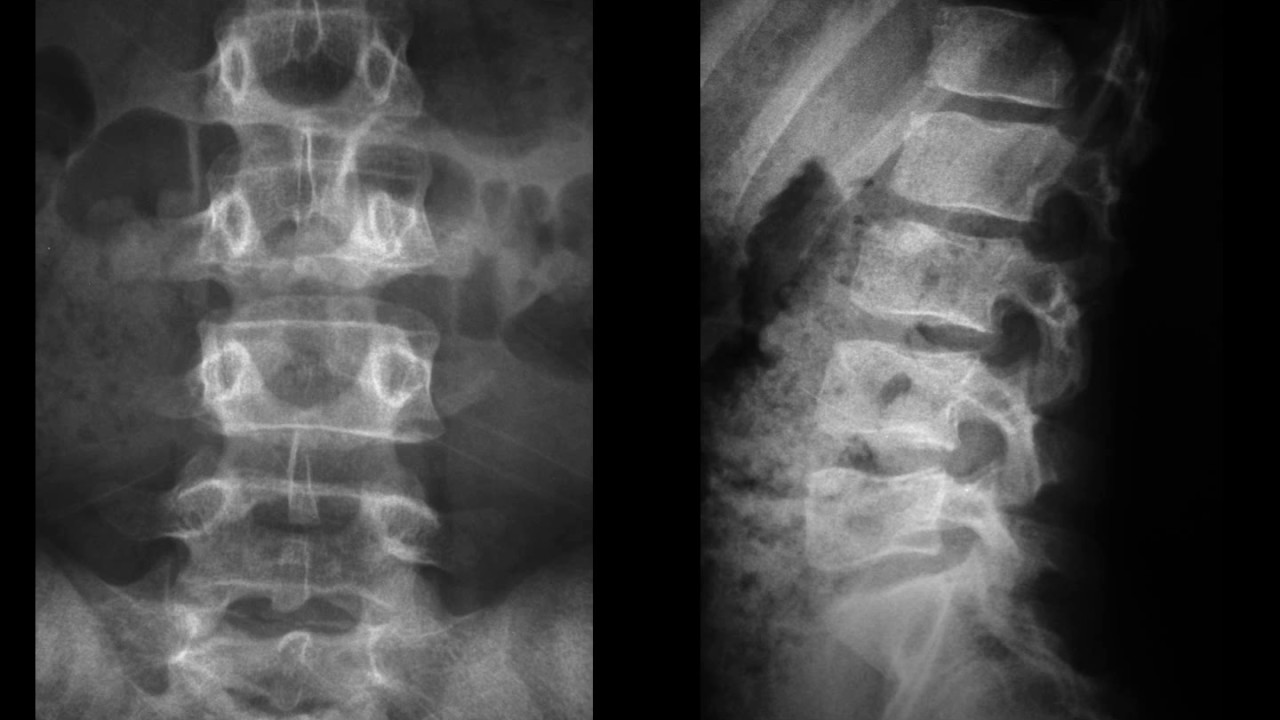

WebLa radiografía de columna lumbar se realiza para evaluar la columna vertebral en la zona lumbar. Se puede utilizar para diagnosticar problemas de la. WebUna radiografía de la columna lumbosacra es una imagen de los pequeños huesos (vértebras) en la parte baja de la columna. Esta zona incluye la región lumbar y el. WebEn la radiografía de columna lumbar lateral se harán evidentes la calcificación y la osificación de los ligamentos longitudinal anterior y posterior, signo de espondilitis. WebLas radiografías de la columna lumbosacra pueden mostrar: Curvas anormales de la columna vertebral. Desgaste anormal del cartílago y huesos de la región lumbar, tales.

WebLa radiografía funcional de la columna lumbar se realiza en la proyección lateral. El paciente está de pie, tocando de lado el soporte vertical de rayos X. Primero,. WebLas “manchas en los pulmones” son opacidades o densidades “blanquecinas” que se ven en la radiografía o TAC de tórax y pueden deberse a distintas. WebRadiografía o rayos X: son buenos para mostrar huesos y grandes estructuras internas, pero no son buenos para mostrar problemas con los “tejidos blandos”. Los tejidos. WebUna radiografía es una prueba rápida e indolora que genera imágenes de las estructuras internas del cuerpo, en especial de los huesos. Los haces de rayos X. WebTomografía computerizada. La tomografía computerizada (TC) es una técnica muy útil para evaluar las anomalías anatómicas de la columna lumbosacra. Ofrece imágenes de. Web¿Que se ve en una radiografía de la columna? La radiografía de la columna se realiza para detectar y diagnosticar lesiones de los huesos, articulaciones y tejidos.

Nuevo Radiografía anteroposterior y lateral de columna lumbar. | Download actualizado